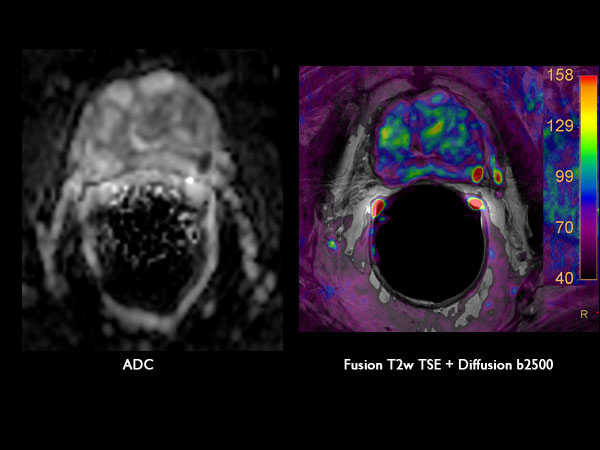

75-year old male. dS Endo coil used to visualize tumor in peripheral gland.

Axial Diffusion